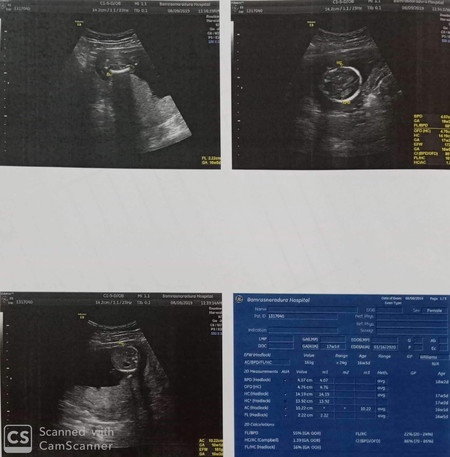

ใช่ผู้หญิงไหมคะ female

อันนี้เป็นเพศของแม่ค่ะ ถ้าเป็นการตรวจอัลตราซาวด์อย่างเดียวจะไม่ระบุเพศลูกลงในเอกสารไม่ว่าจะโรงพยาบาลรัฐหรือเอกชนเพราะ การอัลตราซาวด์นั้นไม่ได้แม่นยำชัดเจน 100% การตรวจอัลตร้าซาวด์เพื่อระบุเพศ อาจมีการคลาดเคลื่อนได้หากลูกขี้อาย หรืออยู่ในท่าที่ทำให้หมอไม่อาจเห็นได้ชัดเจน ทุกโรงพยาบาลจะมีเอกสารให้เราเซ็นยินยอมก่อนการตรวจอัลตราซาวด์ว่าไม่สามารถบอกเพศได้เสมอไป และอาจไม่ถูกต้องทุกครั้งก่อนทำการตรวจ ดังนั้นหมอไม่มีทางลงข้อมูลเพศที่ไม่แน่ชัดด้วยการดูผ่านภาพขาวดำลงในเอกสารทางการแพทย์แน่นอนค่ะ ถ้าจะให้รู้ผลเพศชัดเจนเลยคือการตรวจแบบNIPTค่ะ เป็นการตรวจหาโครโมโซม

Female ด้านบนคือเพศของแม่ค่ะ